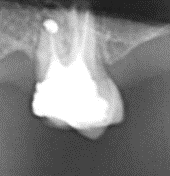

- Albul puternic de pe radiografie poate reprezenta o obturație (plombă), un pivot corono-radicular, un implant, chiar și suprapunerea a doi sau mai mulți dinți

Radiografia dentară poate evidenția, de asemenea, problemele la nivelul implanturilor dentare, care apar ca zone gri intens în jurul implantului.